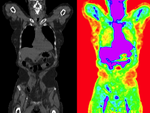

Slicer Registration Library Case #20: Intra-subject whole-body PET-CT

PET-CT, whole-body, change assessment